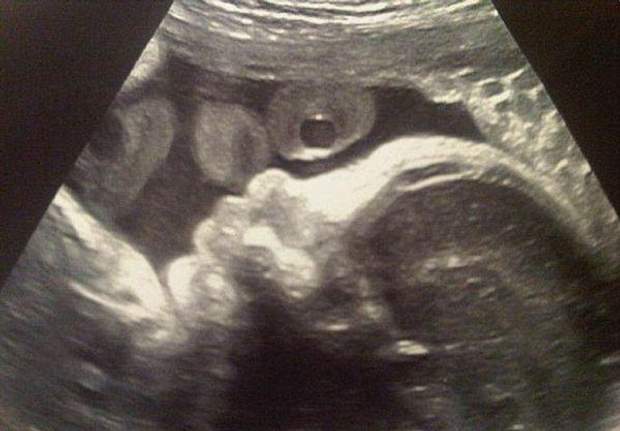

Шакира показала УЗИ своего ребенка (Фото)

Певица Шакира опубликовала в интернете фотографию своей УЗИ.

"Его первая фотография", - подписала УЗИ-снимок Шакира.